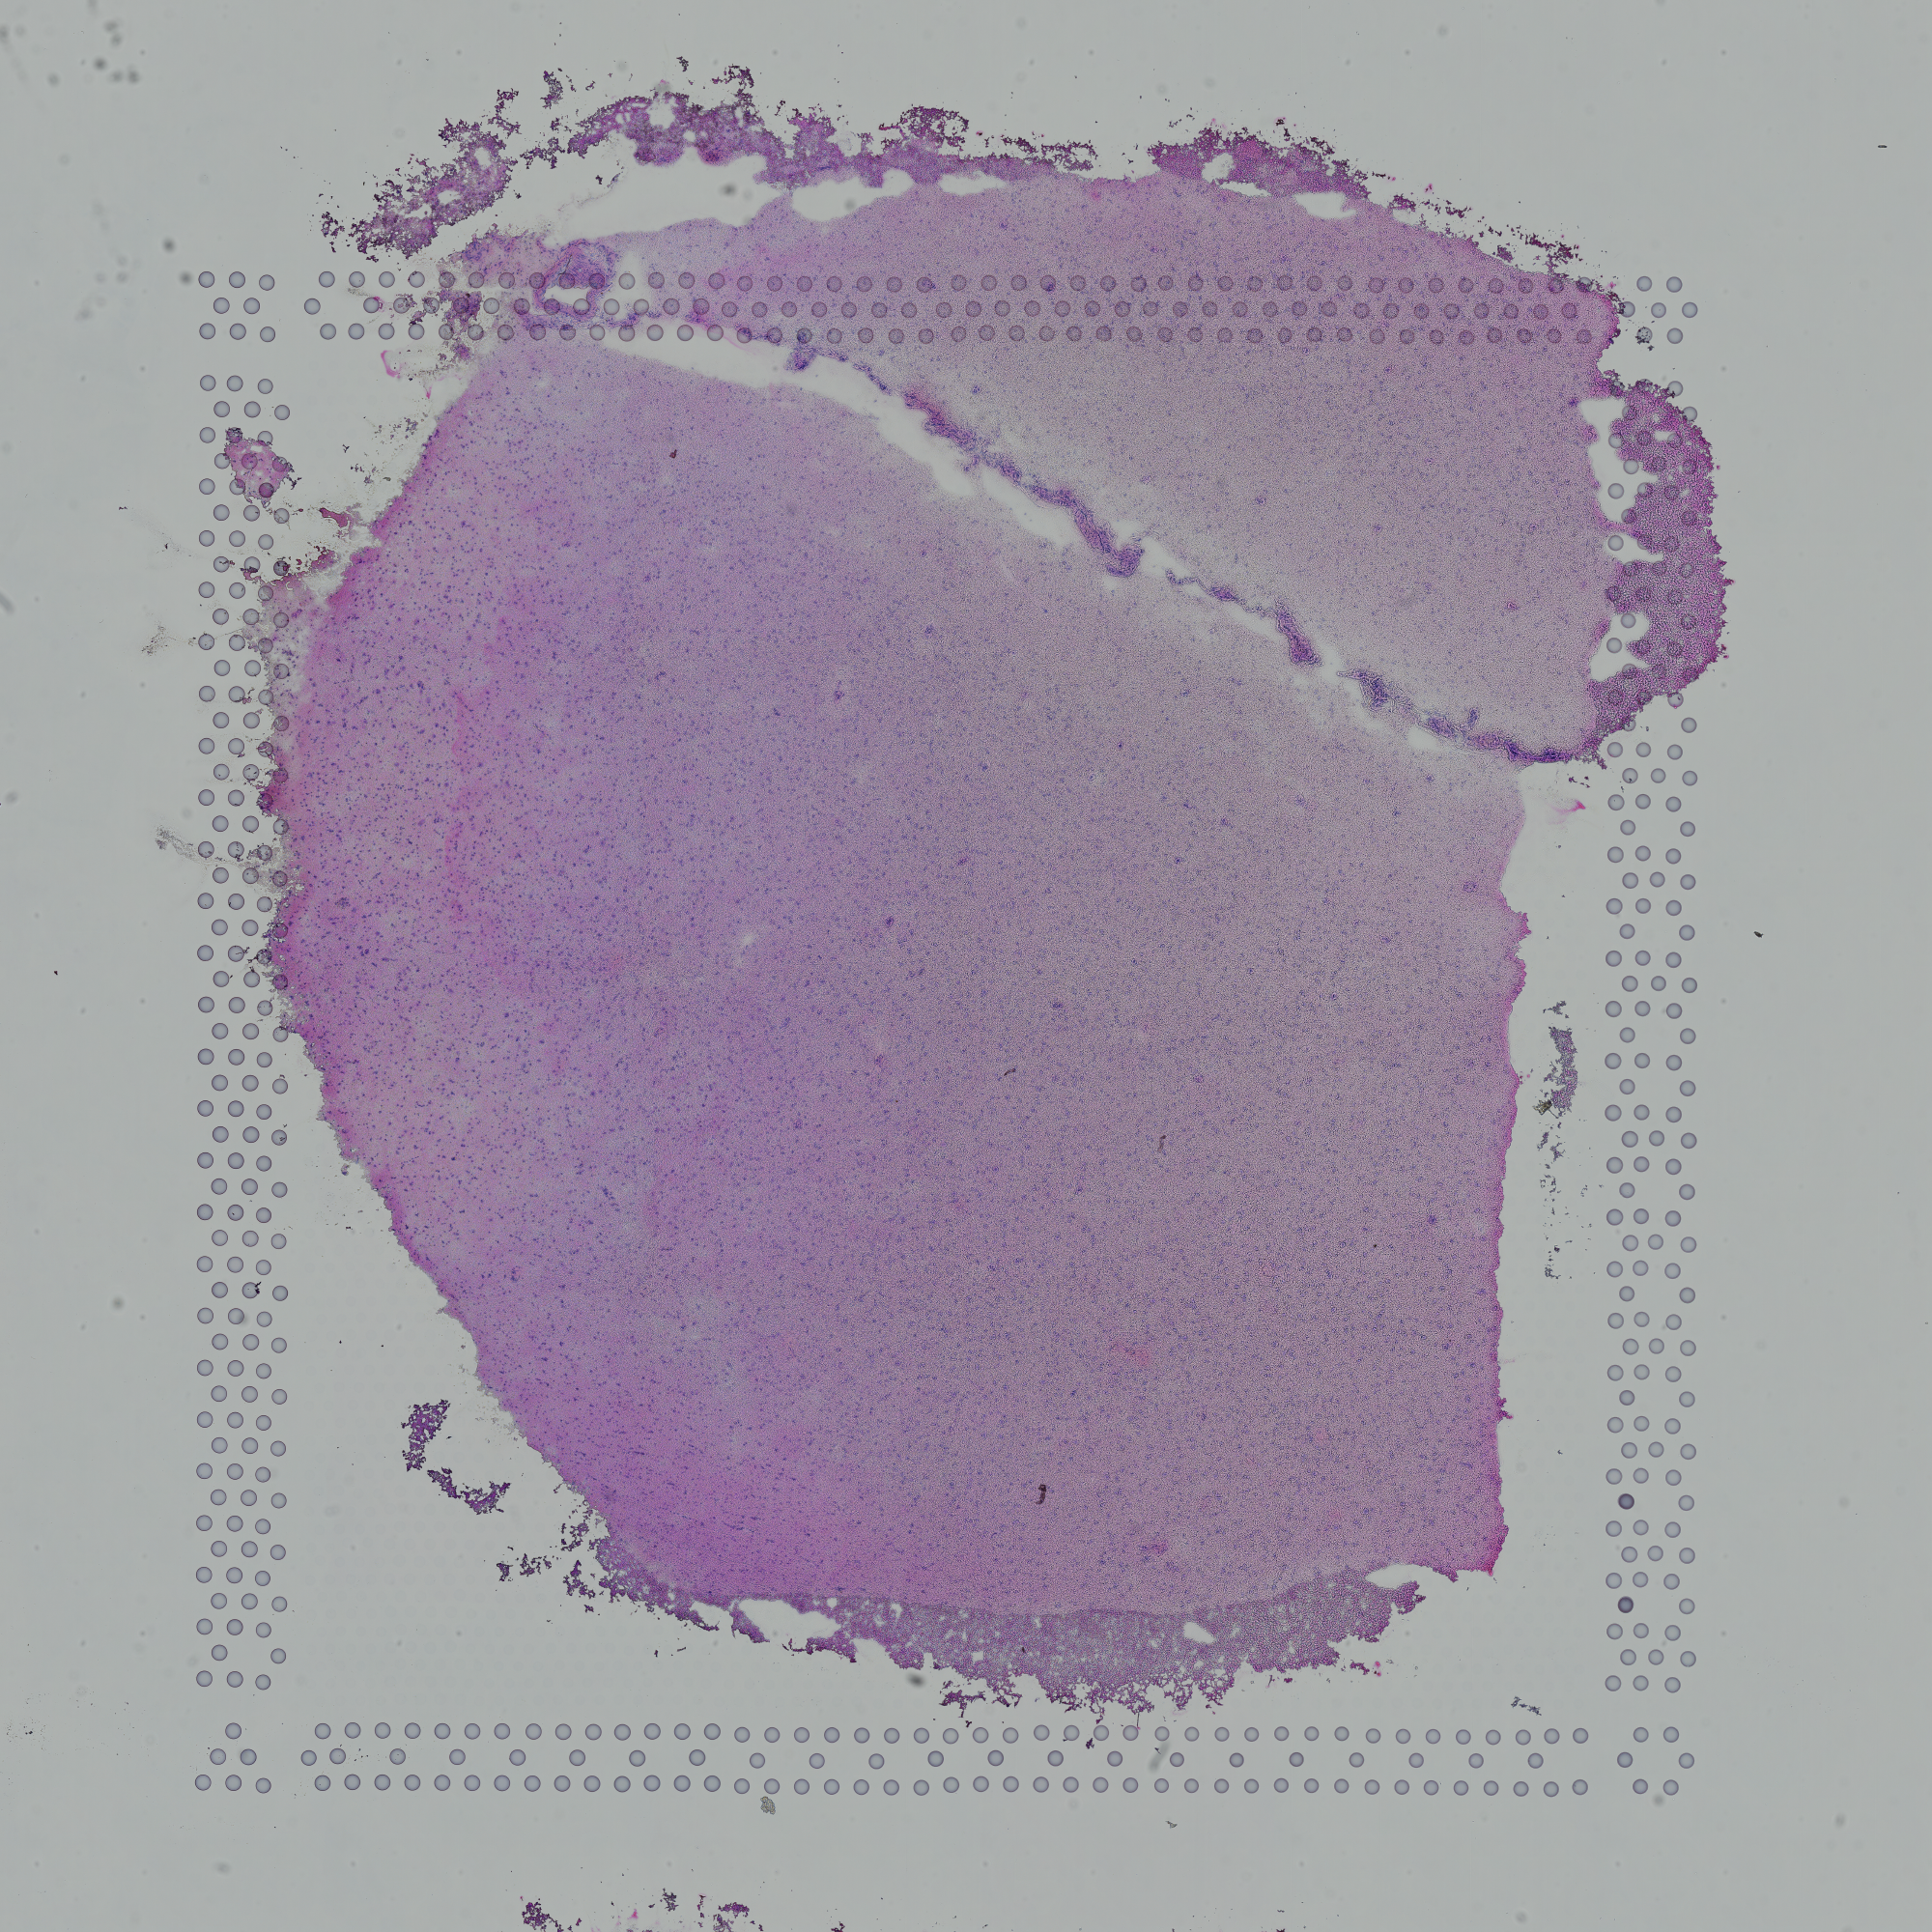

tissue_hires_image.png